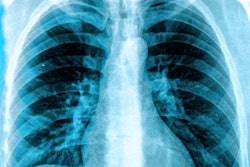

Toge and colleagues developed an automated mathematical algorithm that creates a "biological fingerprint" for an image based on anatomical information in the x-ray. The fingerprints are based on five attributes with distinct anatomic structures, such as cardiac shadow, lung apex, superior mediastinum, right lower lung, and the whole lung field.

The mathematical algorithm examines the biological fingerprint of the misplaced image and searches for a match in the PACS database, using the assumption that two different images of the same patient will be more similar than any images from different patients. By matching the five attributes, it produces a correlation index score, and the image with the highest score is identified as the correct match for the misfiled image.